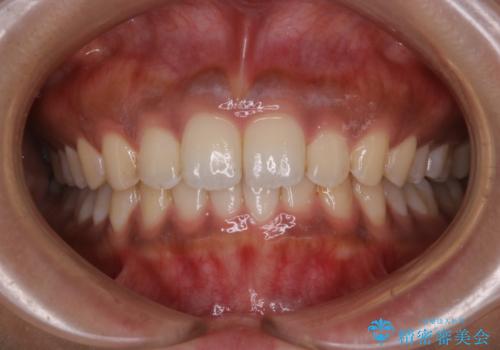

タバコのステインを徹底的に除去

- タバコによるステインを綺麗にしたいとのことでした。

PMTC60分コースを行いました。

タバコに含まれているものの中で、タールというものが歯の黄ばみの原因です。その黄ばみなどを、無理に落とそうとしたりすると歯の表面に傷がついてしまったり余計に汚れがつきやすい状態になることがあります。

PMTCでは、歯の表面の凸凹にミネラルを補給して、ツルツルの表面に仕上げます。定期的にPMTCを行うことにより、歯質の強化になり着色がつきにくい状態になります。